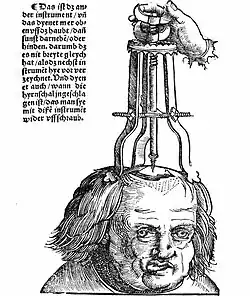

- Along with most other sciences, the first real advances in neurology and neurosurgery after the Greeks occur in the Renaissance. The invention of the printing press allowed the publication of anatomical textbooks, pages, allowing the dissemination of knowledge. An early example is Johann Peyligk's Compendium philosophiae naturalis, published in Leipzig, Germany in 1499. This work contained 11 woodcuts, depicting the dura mater and pia mater as well as the ventricles.[16]

- A revolution took place in both neurology in particular and in anatomy in general when Andreas Vesalius published his De humani corporis fabrica in 1543. It includes detailed images depicting the ventricles, cranial nerves, pituitary gland, meninges, structures of the eye, the vascular supply to the brain and spinal cord, and an image of the peripheral nerves.[16] Vesalius, unlike many of his contemporaries, did not subscribe to the then common belief that the ventricles were responsible for brain function, arguing that many animals have similar systems of ventricles to those of humans but no true intelligence.[17] It appears that he rarely removed the brain from the skull before cutting it, most of his diagrams showing the brain sitting inside a severed head.[18]